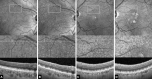

To determine longitudinal changes in choriocapillaris (CC) measures in eyes with reticular pseudodrusen (RPD) using optical coherence tomography angiography (OCTA). In this observational prospective study, 20 patients with exclusively RPD and no other alteration due to age-related macular degeneration were included. Eight RPD patients were re-examined at 5-year follow-up. Multimodal imaging was performed at baseline and at 5-year follow-up. OCTA CC images were analyzed for number, size and total area of flow deficits (FD), mean signal intensity, signal intensity standard deviation and kurtosis of signal intensity distribution in the ring area between a circle of 4 mm diameter and a circle of 6 mm diameter and in the superior ring quadrant. Area affected by RPD increased from 19.36 ± 8.39 mm2 at baseline to 37.77 ± 9.03 mm2 at 5-year follow-up. At baseline, percent of CC FD area was greater in RPD eyes (quadrant: p < 0.001; ring: p < 0.001) compared to controls. Besides, RPD eyes revealed a lower mean intensity signal (quadrant: p < 0.001; ring: p < 0.001). Evaluation of CC parameters suggested significant group × time interaction effects for CC FD (p = 0.04) and mean intensity signal (p = 0.004), in that RPD eyes presented increased CC FD and decreased mean intensity signal at follow-up. OCTA CC decorrelation signal further decreases in RPD patients over 5 years in both RPD-affected and RPD-unaffected macular areas.